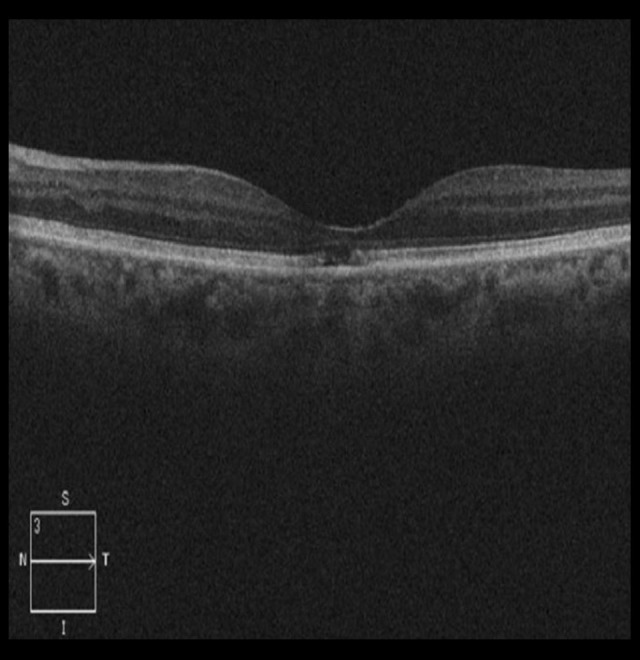

On examination of the left eye, visual acuity was 0.5 LogMAR, fundoscopy showed foveal pigment mobilization, fluoresce-in angiography revealed a hypofluorescent fovea surrounded by irregular hyperfluorescent defects (Figure 1), and SD-OCT showed central foveal thinning with disrupted interdigitation and ellipsoid zones (Figure 2). Other findings from the examination of the left eye were unremarkable.

Figure 2.

Spectral-domain optical coherence tomography of the left eye showed central foveal thinning with disrupted interdigitation and ellipsoid zones, suggestive of acute macular neuroretinopathy.